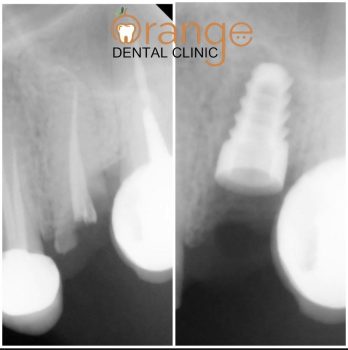

Rusults of Dental Implants